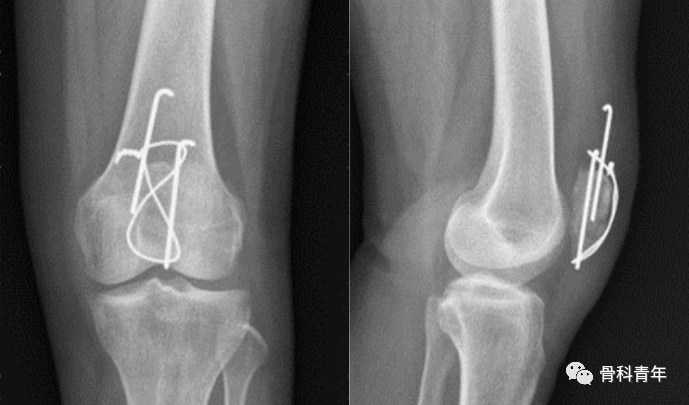

治疗上,尽管克氏针张力带技术一直是髌骨手术治疗的主流,但该技术存在0%-60%的再手术率,且有22%的患者复位丢失。由此可见,并非所有的髌骨骨折均适用于克氏针张力带技术。近年来,髌骨骨折钢板螺钉固定的应用逐渐增多,本文将髌骨骨折的诊断及现有的治疗理念作一总结。

张力带固定是髌骨骨折最主流的固定方法,通过将前方的张力转变为骨折块间压力。具体步骤如下图所示:

有学者进行生物力学发现,在膝关节屈曲时,关节面压力并未增加,但在膝关节屈曲时关节面会产生裂隙。因此把克氏针固定认为是“静态加压”,而非“动态加压”。克氏针的置入位置,在矢状面上应位于髌骨后1/3,才能达到良好的张力带作用。

与克氏针张力带相比,采用空心螺钉替换克氏针,也可以取得良好的功能结果,甚至在文献中有报道空心螺钉张力带内固定强度优于克氏针张力带。

空心钉钛缆固定

但克氏针张力带导致的退针问题仍不可忽视。为了避免这个问题,有学者采用缝线替代钢丝,空心螺钉替代克氏针,取得了良好效果。在一项纳入949例患者的meta分析中发现,张力带固定的并发症发生率更高,采用替代固定方法治疗的患者具有更好的屈曲活动范围、疼痛评分(视觉模拟评分)和膝关节功能评分。

克氏针退出

总的来说,与克氏针固定相比,空心螺钉张力带固定有较低的再手术率和改善的功能评分,在生物力学测试中的初始强度和周期性负荷方面表现也更好。